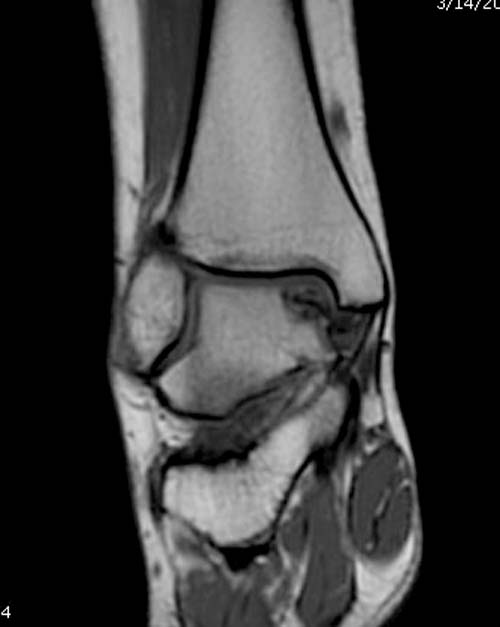

Разбираемый случай не имеет ничего общего с классическим Аваскулярным Некрозом Таранной кости. Здесь так назывемый (osteochondral defect) или osteochondritis dissecans (OCD) таранной кости, при котором патология локализуется в медиально-верхнем нагрузочном отделе. В основном OCD

встречается после хронической травмы, но бывают случаи врожденного генеза, которые обнаруживаются при случайных исследованиях.

Симптоматология  OCD выражается слабым отеком, а более сильные боли наступают после физической нагрузки. В отличие от АВН тарана, когда боли постоянные, а при OCD боли изчезают после отдыха. В начальных стадиях

на рентгенограммах не всегда заметны склерозные участки, и поэтому в большинстве диагноз устанавливается поздно. Приход КТ и МРТ улучшил диагностику, и в срезах внутри кисты можно увидеть жидкость, но это не означает проявление симптоматологии. Симптомы проявляются с момента образования внутрисуставных краевых фрагментаций!